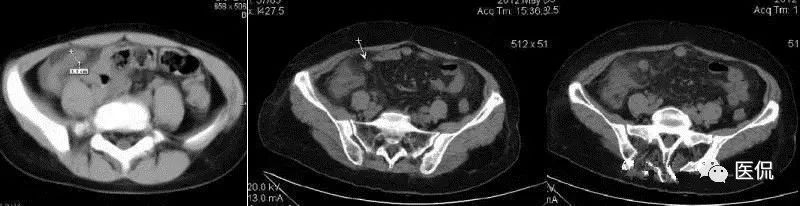

(2)CT:阑尾扩张,管径>6mm,壁增厚,增强强化。阑尾周围炎,周围(脂肪)“条纹征”即周脂肪内斑点/条纹状模糊英、局部筋膜增厚、系膜密度增高等。阑尾粪石,其他有盲肠增厚、阑尾周液体积聚、“箭头征”(肠道内造影剂汇集在盲肠尖端(阑尾起始部)形成箭头样或鸟嘴样改变)。

(2)CT:类似急性阑尾炎。阑尾扩张(管径>6mm)、阑尾尖端增厚、粪石、网膜系膜组织密度增高粘连、淋巴结肿大、“箭头征”、脓肿、蜂窝织炎、积液

(2)CT:右下腹/盆腔囊性肿块,壁薄或厚,增强环形强化,内部可见粪石;也可为边界不清、密度不均软组织影,强化不明显。肿块与盲肠关系密切,与周围结构粘连,内可见小气泡/气液平面。临近肠曲反射性淤积,可伴气液平面。